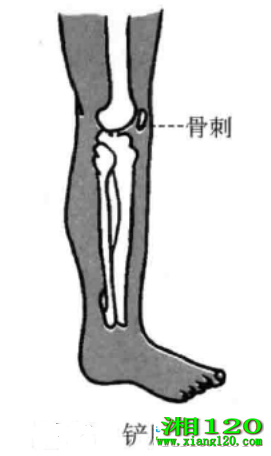

5、铲磨削平法

当骨刺长于关节边缘或骨干,并且骨刺较大时,将刀口线沿骨刺竖轴线垂直刺入,刀口接触到骨刺后,将骨刺尖部或锐边削去磨平。